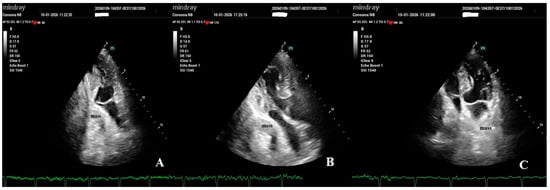

Extrinsic Left Atrial Compression: An Echocardiography-Guided Diagnosis Illustrated by Two Clinical Cases and a Structured Review of Published Cases

Background: Extrinsic compression of the left atrium (LA) is a rare and underrecognized condition that may result in significant hemodynamic compromise and atrial arrhythmias. The available evidence has been largely limited to isolated case reports and small case series, and clinical awareness has remained low. Methods: We performed a structured review of published case reports and case series indexed in PubMed between 2016 and 2026 describing extracardiac LA compression. A predefined and reproducible literature search strategy with explicit eligibility criteria was applied. The structured review included 22 publications reporting 23 individual cases of LA compression; in addition, two institutional cases with distinct etiologies were presented separately. Demographic characteristics, presenting symptoms, diagnostic modalities, complications, management strategies, and outcomes were synthesized descriptively. Results: The structured review identified gastroesophageal disorders, particularly hiatal hernia, as the most frequent etiology, followed by vascular, mediastinal, malignant, and musculoskeletal causes. Dyspnea was the most common presenting symptom, while hemodynamic compromise, pulmonary edema, and atrial arrhythmia represented the most frequent complications. Transthoracic echocardiography was the initial diagnostic modality in all reported cases, with computed tomography required for definitive etiological diagnosis. The two institutional cases illustrated both a common cause, hiatal hernia mimicking intracardiac mass, and a rare, aggressive malignant cause with extensive mediastinal involvement. Conclusions: Extrinsic LA compression arises from diverse extracardiac pathologies and may be clinically severe. Transthoracic echocardiography can serve as a pivotal first-line tool for early recognition and differentiation from intracardiac masses, while cross-sectional imaging is essential for etiological clarification. By integrating institutional experience with a structured synthesis of published cases, this review can provide practical insights to support timely diagnosis and management of this potentially life-threatening condition.